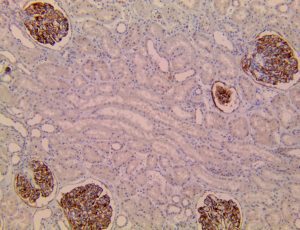

This activation induces inflammatory monocytes to highly express IL-6, starting a localized and then systemic cascade effect that results in hyperproduction of IL-6, which accelerates the inflammatory process. Because IL-6 also increases vascular permeability, excessive levels cause blood vessels to become very leaky. This, along with clotting factors released from vascular endothelial cells, stimulates the coagulation cascade, resulting in microthrombosis (tiny clots), which leads to ischemia and tissue death of the kidney, intestines, heart, liver, brain and extremities.